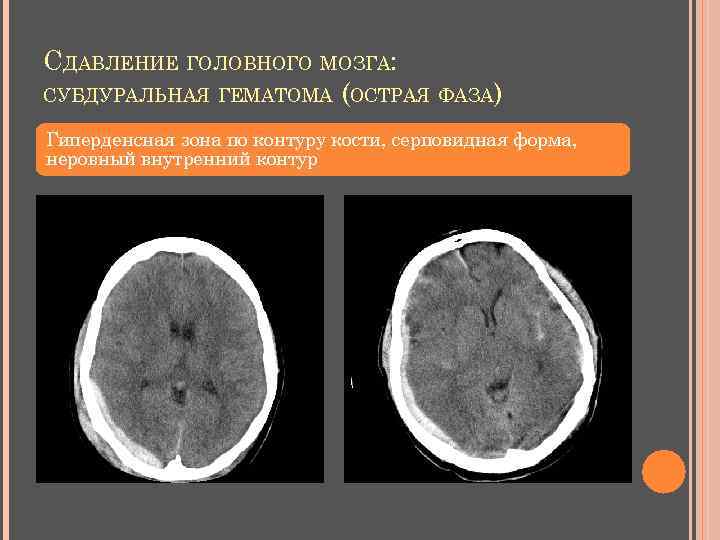

СУБДУРАЛЬНАЯ ГЕМАТОМА КТ (острая): гиперденсная зона по контуру кости, м. б. затек на намет мозжечка, серповидный отросток серповидная форма четкий наружный, неровный внутренний контуры острые края «масс-эффект» - смещение срединных структур больше толщины гематомы структура и плотность зависят от давности длина: ширина = 10: 1

СДАВЛЕНИЕ ГОЛОВНОГО МОЗГА: СУБДУРАЛЬНАЯ ГЕМАТОМА (ОСТРАЯ ФАЗА) Гиперденсная зона по контуру кости, серповидная форма, неровный внутренний контур